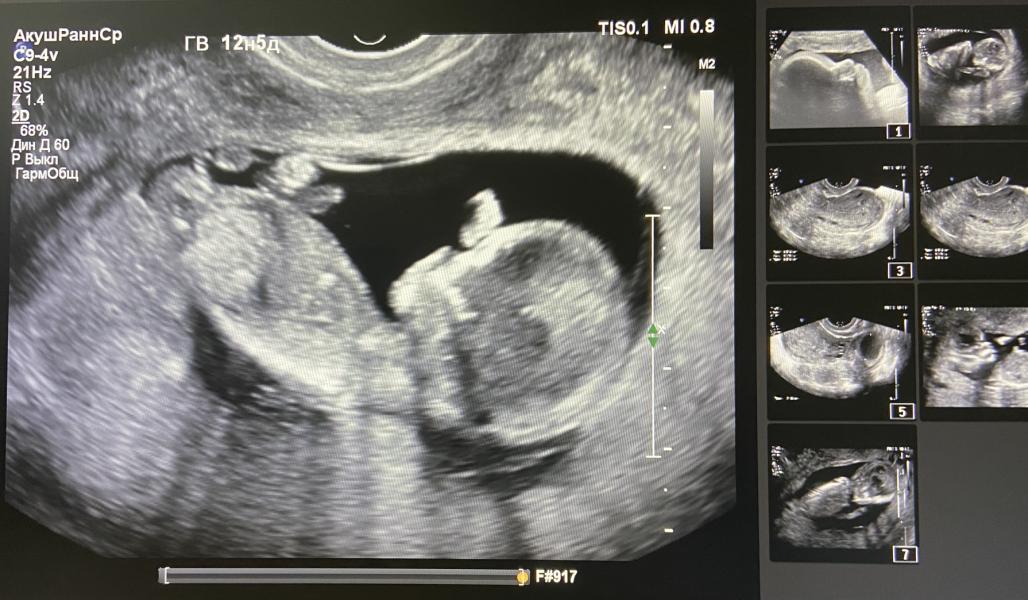

Вчера была на первом скрининге ,вот такой прекрасный малыш у меня сидит 😍 а на втором фото , это она мне показывала что у меня мальчик, он завернул ножки , а это получается вид с попы😅

Врач конечно предупредила что это может нас обманули и на 20 недели уже точно буду знать 😇

А сколько тут недель ?